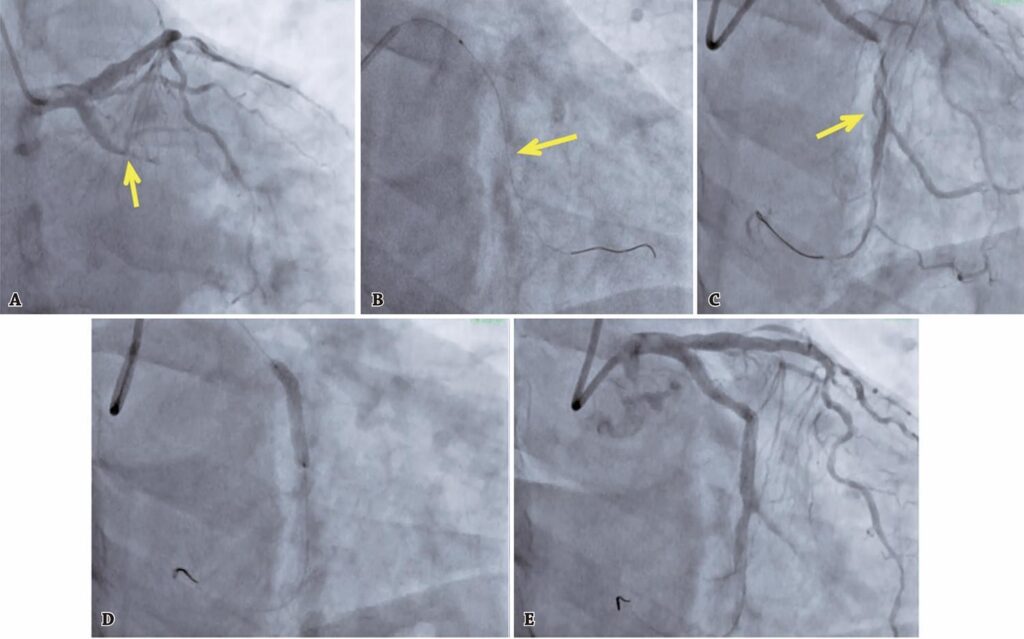

Various factors, including improved therapeutic interventions and advanced technologies, have led to better clinical outcomes for complex percutaneous coronary interventions. However, complications can still occur and have a negative impact on patient survival and healthcare costs. The risk of these complications can be reduced through experienced operators and preventative procedures. This article discusses a case series of five patients with specific periprocedural issues, such as coronary perforation, dissections, abrupt closure of the coronaries, and no-reflow phenomenon.